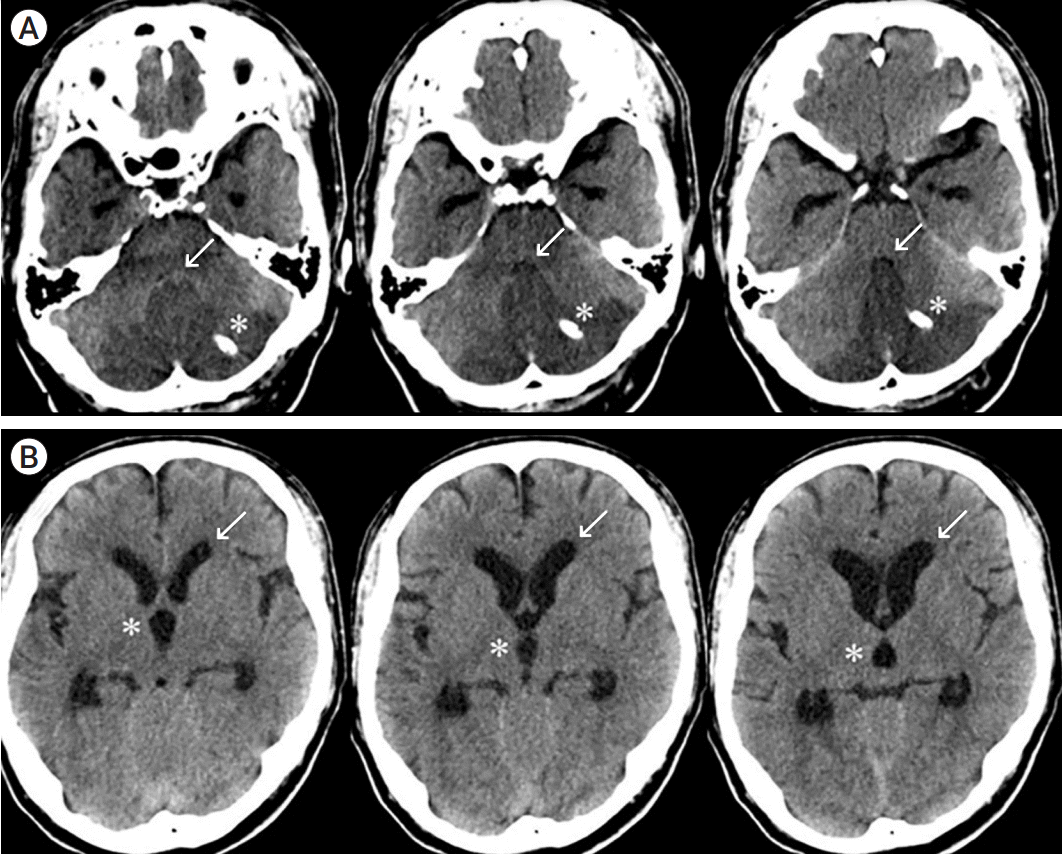

Fig. 4.

After 7 days, CT shows more improvement in the mass effect. (A) The arrow shows a dilated fourth ventricle, and the asterisk shows reduction of the lateral ventricle anterior horn expansion. (B) The asterisk shows favorable changes in the third ventricle dilatation, and the arrow indicates a normal-sized lateral ventricle anterior horn. CT, computed tomography